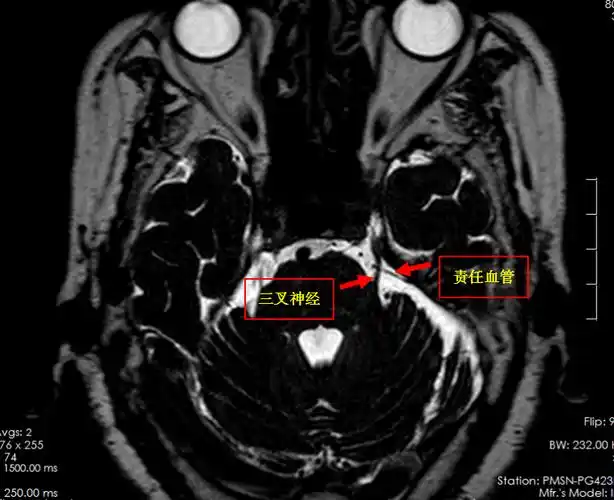

【影像技术】磁共振(mri)三叉神经,面神经,听神经(内听道)扫描技术

三叉神经核磁共振3d-ciss检查显示,患侧三叉神经有血管压迫

术中,医生发现一根动脉血管正压迫三叉神经,这就是患者疼痛的原因.